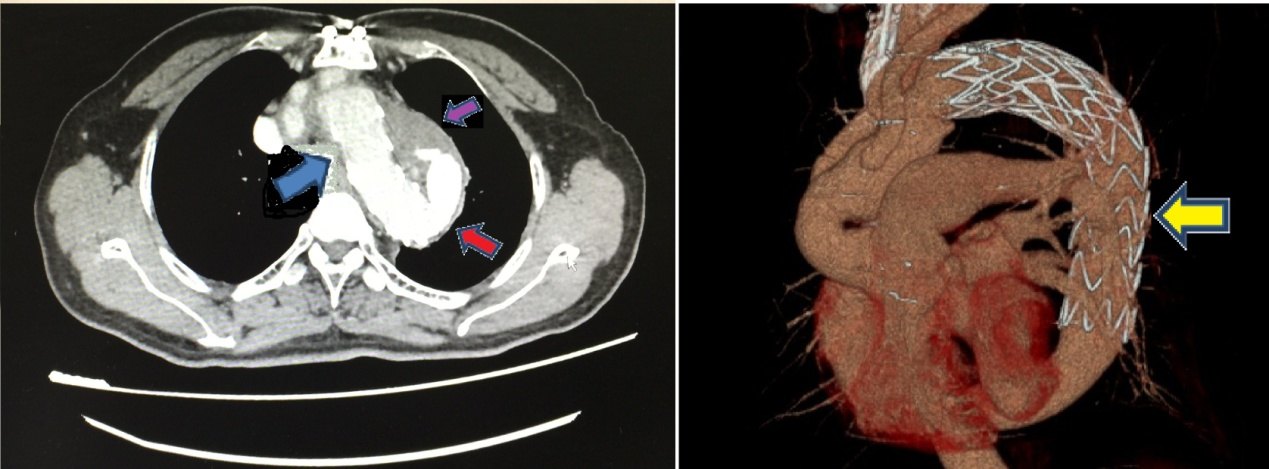

annthoracsurg安贞医院刘迎龙等发现支架象鼻技术替代治疗逆行性a型主

主动脉夹层:保留头臂干的全弓置换联合支架象鼻术

bentalls联合全弓置换及血管内支架象鼻手术